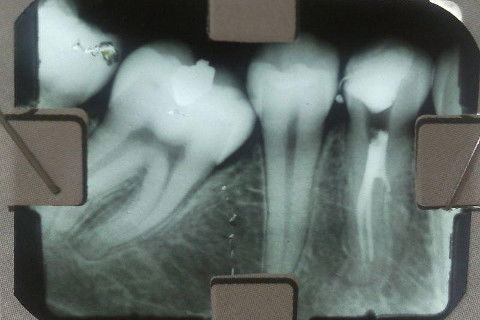

Pré-Molar Inferior com 2 Canais

Aqui vão alguns casos de pré-molares inferiores que tratei com 2 condutos.

Estou meio espantada com a quantidade de casos! Agora antes de começar o tratamento, quando é 1o. pré inferior sempre observo beeeeem o rx para ver se é uni ou bi!!!